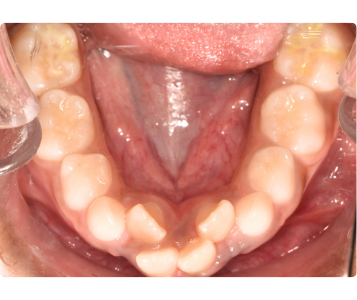

Before and After: Expanding the Airway, Expanding Possibilities

Our before-and-after cases clearly show the power of airway-driven orthodontics. After treatment, the palate is wider, the airway is larger, and the child experiences better sleep, improved focus, and enhanced overall wellness.